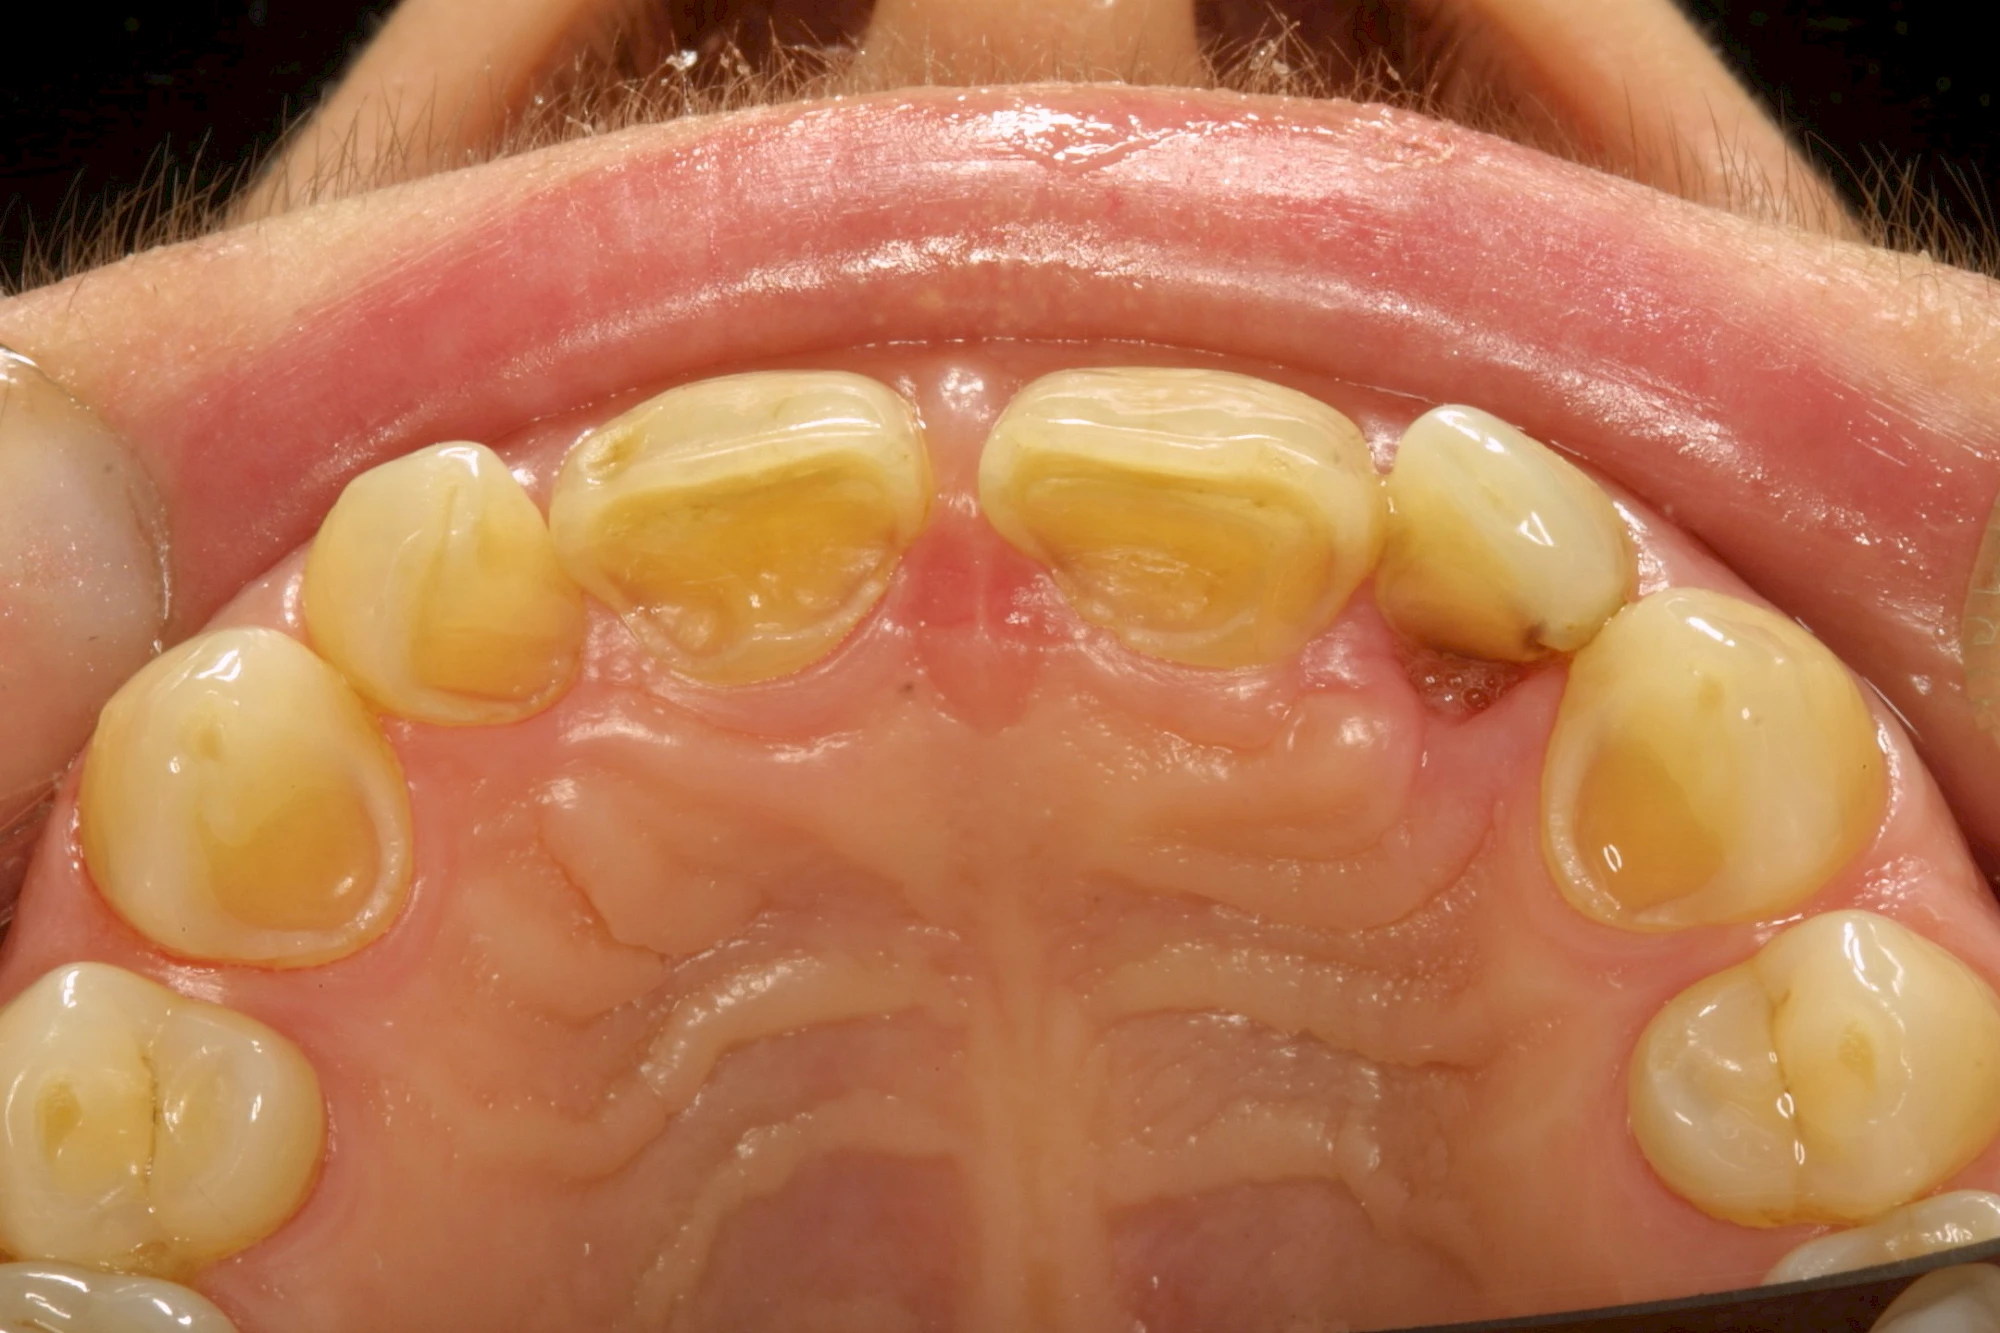

Auswaschung (Erosion) dagegen ist eine Verschleißerscheinung der Zähne aufgrund von immer wiederkehrenden Säureangriffen durch die Nahrung, verstärkt zum Beispiel durch den Genuss säurehaltiger Getränke oder Speisen. Auch bei Menschen mit einer Essstörung (z. B. Bulimie) können die Zähne durch die Magensäure ausgewaschen erscheinen.

Keilförmiger Defekt

Eine Sonderform sind sogenannte keilförmige Defekte im Bereich der Zahnhälse. Hier geht man davon aus, dass Knirschen und Pressen in Kombination mit falschen Putzgewohnheiten (zu hoher Putzdruck, Verwendung von Zahnpasta mit hohen Abrasionswerten) eine Rolle spielen.